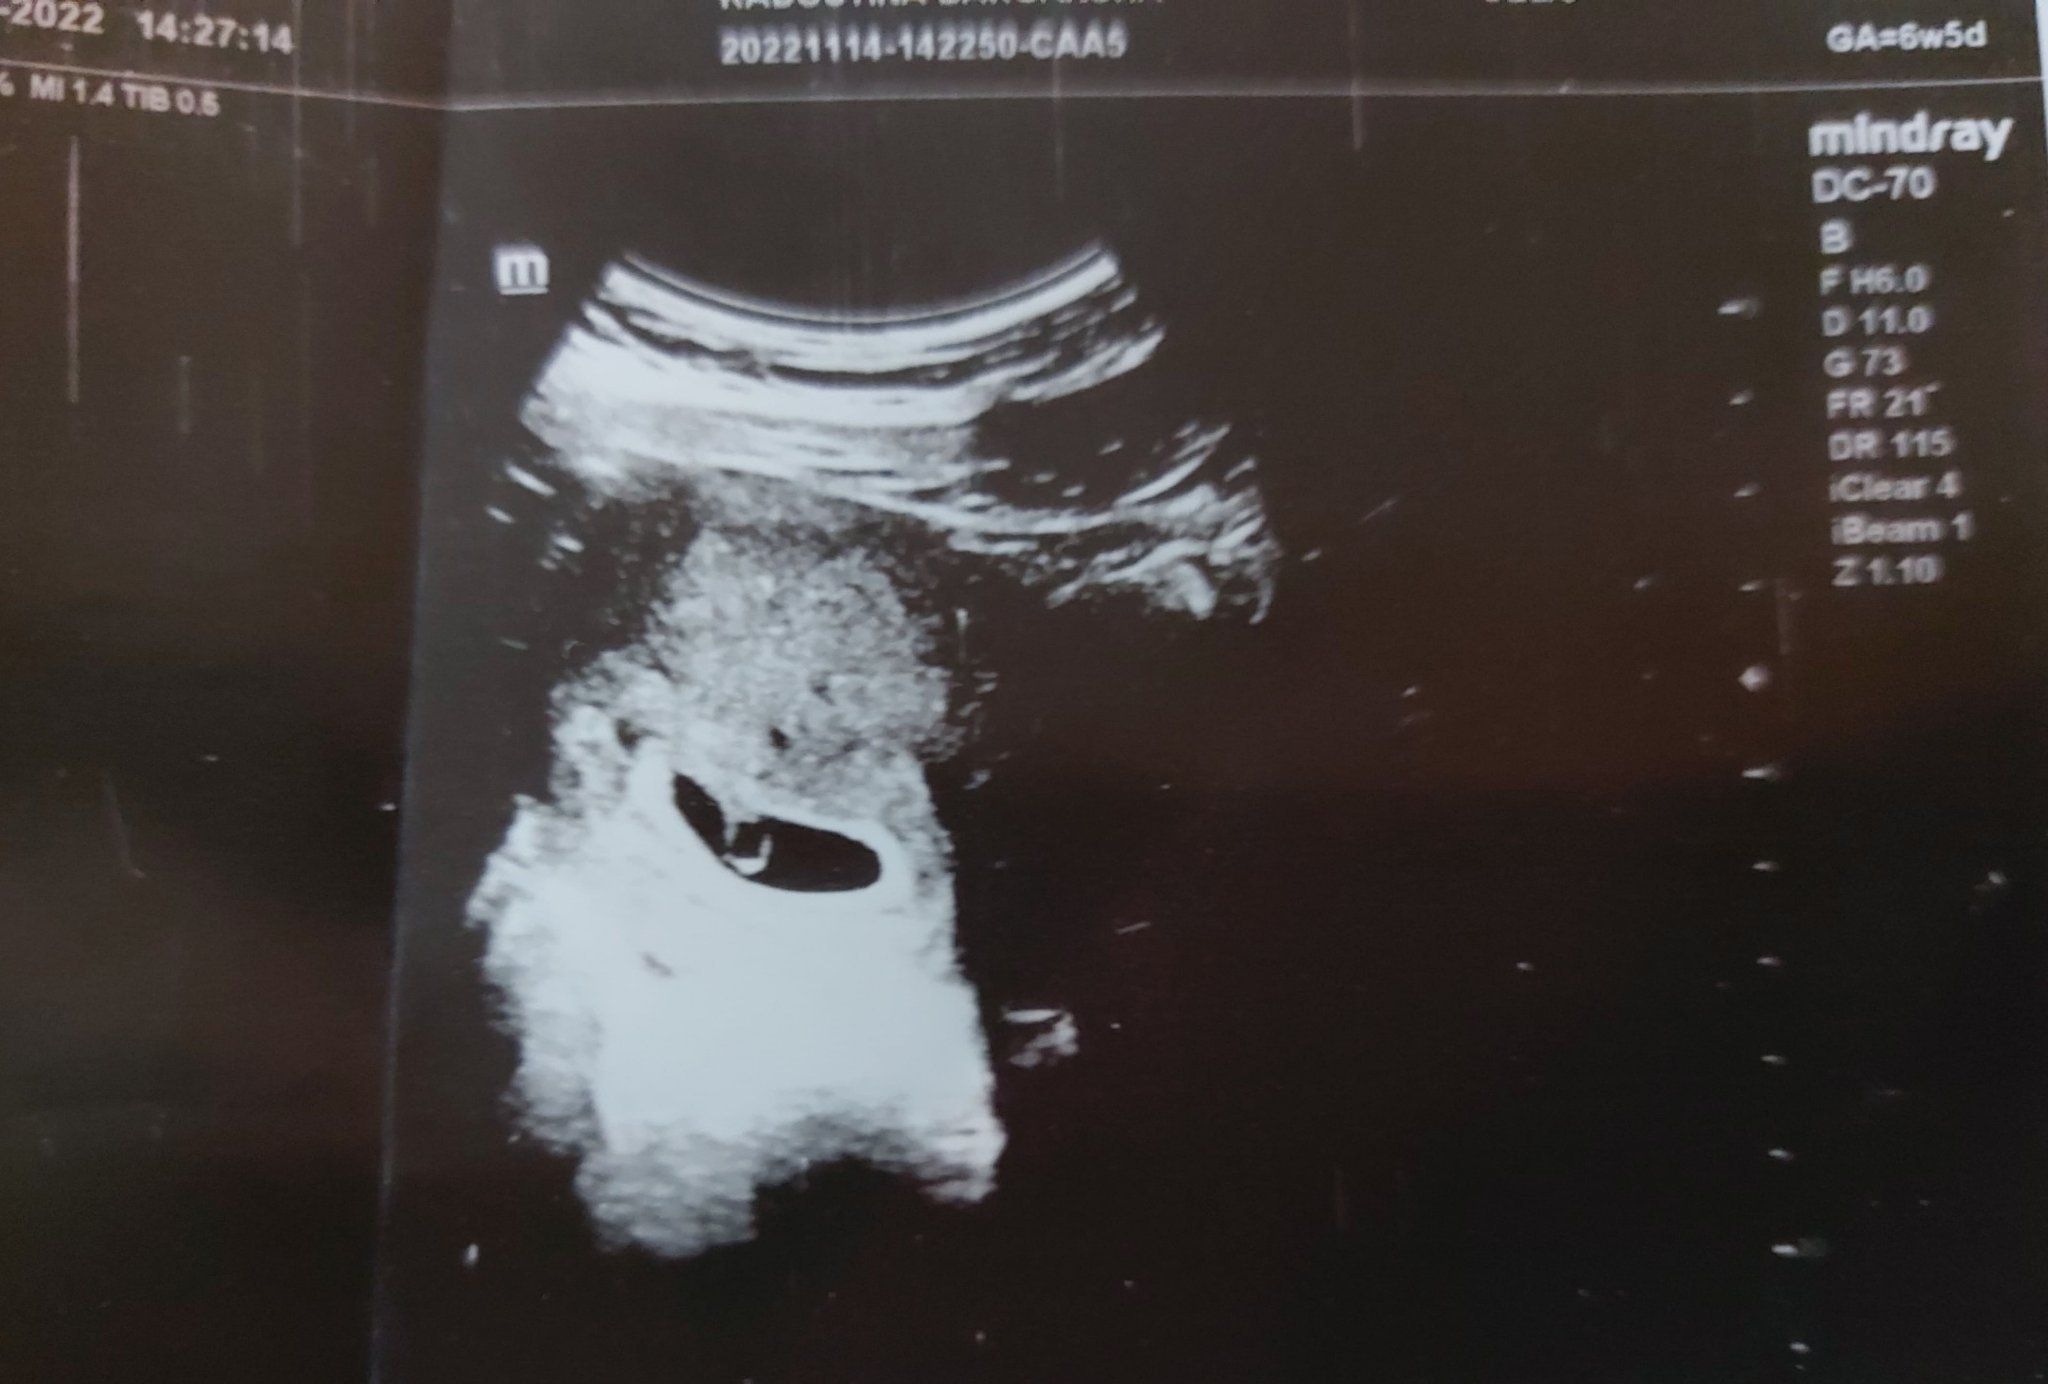

Здравейте! Днес бях на преглед 6w5d - на ехографа се видя сакче, но не и ембрион. Доктора каза, че е рано още за ембрион,но вс изглежда наред, да отида пак след месец... същевременно имам бледо кафеникаво зацапване, въпреки, че пия утрогестан не спира. По мааалко, но всеки ден. Какво мислите?

има ембрион. Смени лекаря

Последна редакция: пн, 14 ное 2022, 21:54 от Margaritka_89

Благодаря за отговора. Всъщност имам голямо доверие на лекаря, от предходна бременност, но днес малко ме претупа сякаш. А с такова нетърпение очаквах прегледа, и не случайно изчаках почти до 7гс с идеята да видим точно ембриончето.

Това е най-вероятно жълтъчно мехурче, не е ембрион.